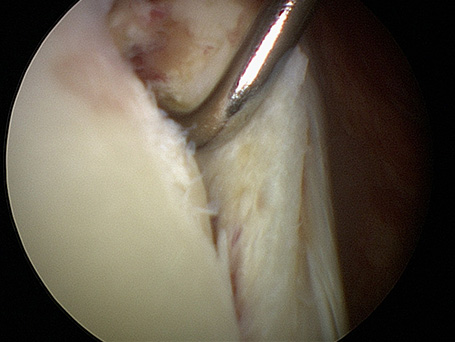

Ein Einriss oder Abriss des Kapsel-Labrumkomplexes führt zur Störung des Gelenkes. Die geschädigte Gelenkkapsel führt nicht mehr den Oberarmkopf. Das Gelenk ist in Richtung der geschädigten Gelenkkapsel instabil. Die beiden häufigsten Verletzungen des Labrums sind die SLAP Läsion (superior labrum from anterior to posterior) und die Bankardläsion.

Bankart Läsionen sind Kapselabrisse, die typischerweise bei Schulterluxationen entstehen. Sie finden sich meist am vorderen unteren Pfannenrand. Je nach Richtung der Verrenkung der Schulter können Verletzungen des Kapsel-Labrumkomplexes sowohl vorn, als auch hinten auftreten (hintere Instabilität).

Junger Patient mit dorsaler Instabilität nach vorangegangenem Trauma und dorsalem knöchernem Pfannenrandabbruch. Intraoperativ bereits völlig fest verheiltes Knochenfragment. Stabilisation mit Reschspan über arthroskopisch gestützte Technik mit funktionell unauffälligem schmerzfreiem klinischen Ergebnis .